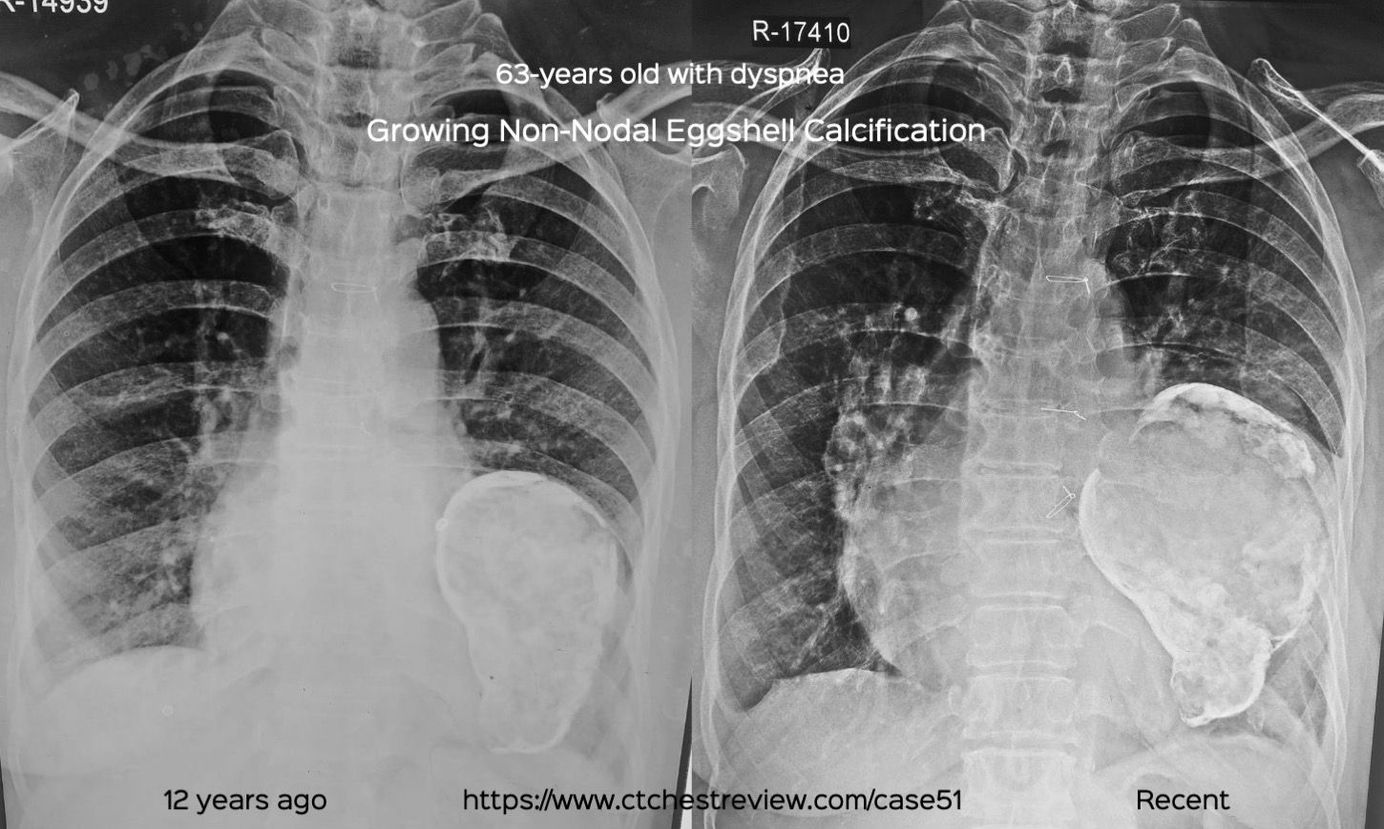

This 63-years old came with these two radiographs of a growing mass in the left hemithorax showing eggshell calcification

I have written and spoken about nodal eggshell calcification in Case 45 and Case 30 earlier. This patient had non-nodal eggshell calcification that typical occurs with tumors, cysts, aneurysms.